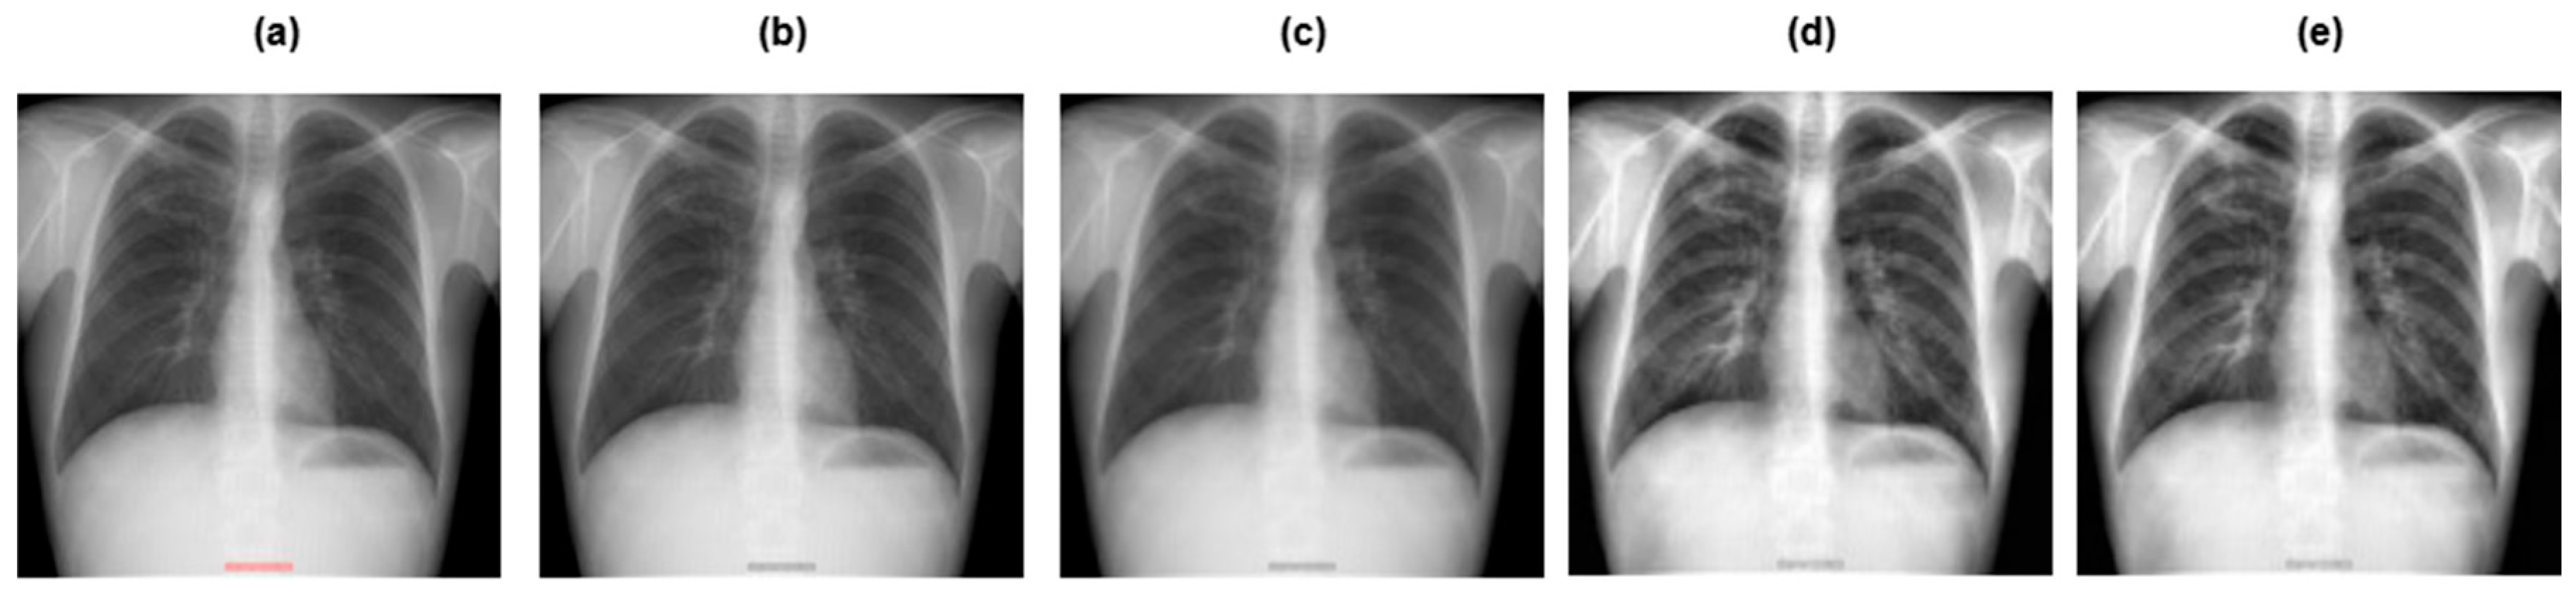

3.2. Data Preprocessing

- •

- Grayscaling: This refers to the conversion of RGB images to grayscale.

- Image resizing: The grayscale image was rescaled to a particular size, that is 128 × 128 pixels.

- Contrast Limited Adaptive Histogram Equalization (CLAHE): This improves the contrast of the image, making the tuberculosis area more pronounced and clearer.

- Image normalization: Normalization adapts the intensity range of individual pixels, typically to make the pixel values of an image more consistent and uniform to the human eye.

3.3. Data Augmentation